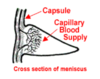

Other extrasynovial structures inclue the menisci.

The menisci are intracapsulr but extrasynovial. Why aren’t they lined by synovium? - the synovium is located at the margins only.

The menisci are articulating directly with the femur condyles. Thus they recieve lots of sheering stress (protect the bones)

It they were lined by synovial membrane, it risks tearing, damage and bleeding into the joint (haemarthritis). Thus is because synovium has a dense net of small blood vessels that provide nutrients.